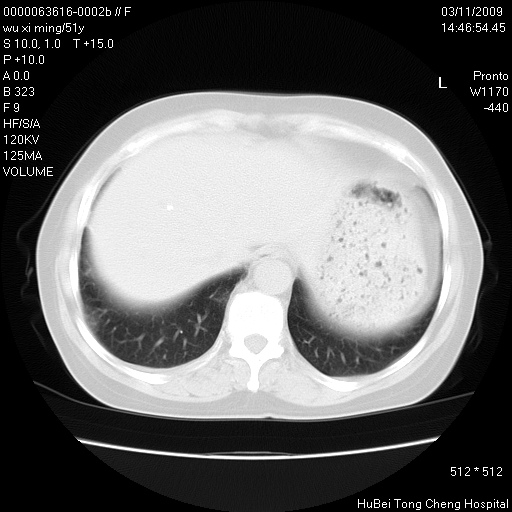

患者 女,51岁。因“胆囊炎,胆囊结石”,行常规术前胸部x线检查发现:右上肺结节病灶,建议行进一步检查。患者无咳嗽、咳痰及咯血等呼吸道症状,近期出现背部疼痛不适。

胸部ct轴位平扫(层厚10mm,螺距1.5,重建间隔10mm;部分层面:层厚3mm,螺距1.0,重建间隔3mm),图像如下: